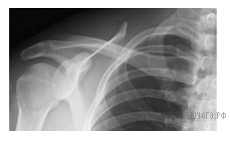

Какой сустав человека изображен на рентгеновском снимке?

1) тазобедренный

2) коленный

3) плечевой

4) локтевой

Ответ: